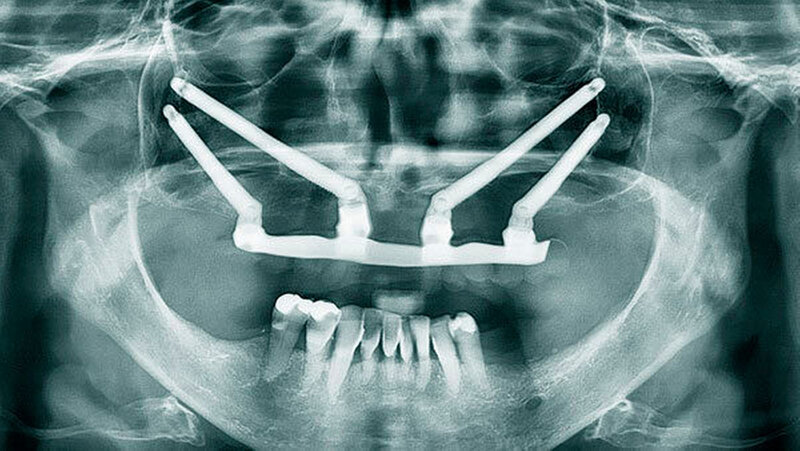

Bei der Sofortversorgung nach dem All-on-4 Konzept (Abbildung 1a-d) werden die frontalen Implantate gerade inseriert und axial belastet, die distalen in der Regel anguliert (Abbildung 2). Durch die Angulation kann ein externer Sinuslift im Oberkiefer umgangen und eine ausreichende Primärstabilisation für eine Sofortversorgung erreicht werden. Im Unterkiefer verhindert das Foramen mentale bei gerader Insertion häufig eine dorsale Positionierung der Implantate. Durch die Angulation der distalen Implantate werden das Belastungspolygon optimiert und ausgeprägte distale Cantilever (Extensionsbrücken) vermieden.

Eine erhebliche Erweiterung der Indikation des All-on-4 Konzeptes konnte durch den Einsatz von Zygoma-Implantaten erzielt werden. Zygoma-Implantate werden im Os zygomaticum verankert und erreichen auch in Situationen mit starker Kieferkammatrophie eine hohe Primärstabilität. Herkömmliche augmentative Verfahren können so vermieden werden. Zygoma-Implantate wurden zunächst bei Patienten mit besonderen Dysplasien im Kieferbereich und bei Tumorpatienten nach Resektion von Kieferanteilen eingesetzt. Balshi war einer der ersten Kliniker, der mit speziell gestalteten Implantaten entsprechende Fälle versorgte. Die Übertragung des All-on-4 Konzeptes auf Zygoma-Implantat-getragene Versorgungen ist insbesondere mit dem Namen Malavez verbunden, die sich sehr um diese Technik verdient gemacht hat. Dieses Konzept auf Zygoma-Implantaten wird angewendet in Fällen mit ausgeprägter Kieferkammatrophie im Oberkiefer (Abbildung 4a). Die Zygoma-Implantate werden in aller Regel in ITN inseriert. Lediglich ein externer Sinuslift ist als augmentative Maßnahme notwendig (Abbildungen 4b und c). Durch dieses Vorgehen können aufwändige augmentative Verfahren umgangen werden. Die prothetische Versorgung der Zygoma-Implantate entspricht dem Vorgehen wie beim All-on-4 Konzept und erfolgt einen Tag postoperativ. Erreicht wird, wie beim ursprünglichen All-on-4 Konzept, eine festsitzende Sofortversorgung (Abbildungen 3 und 4d).